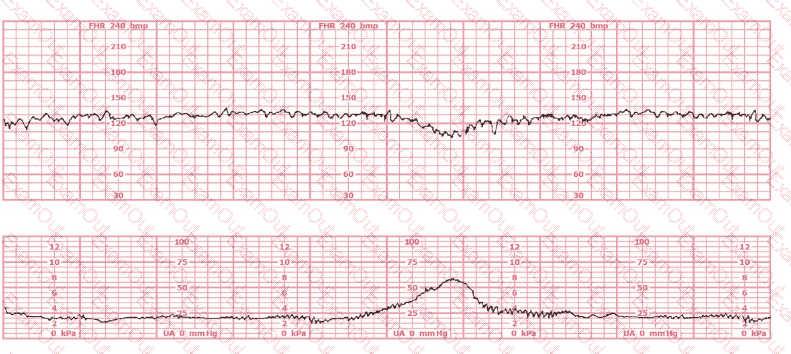

A woman at 39-weeks gestation is in early labor, 2–3 cm dilated, 85% effaced, and –2 station. Based on the fetal heart rate tracing shown, what is the most appropriate first intervention?

Based on the tracing shown, the first action should be to

palpate for contractions

The pattern on the fetal heart rate tracing shown is likely due to

fetal head compression

placental insufficiency

umbilical cord compression